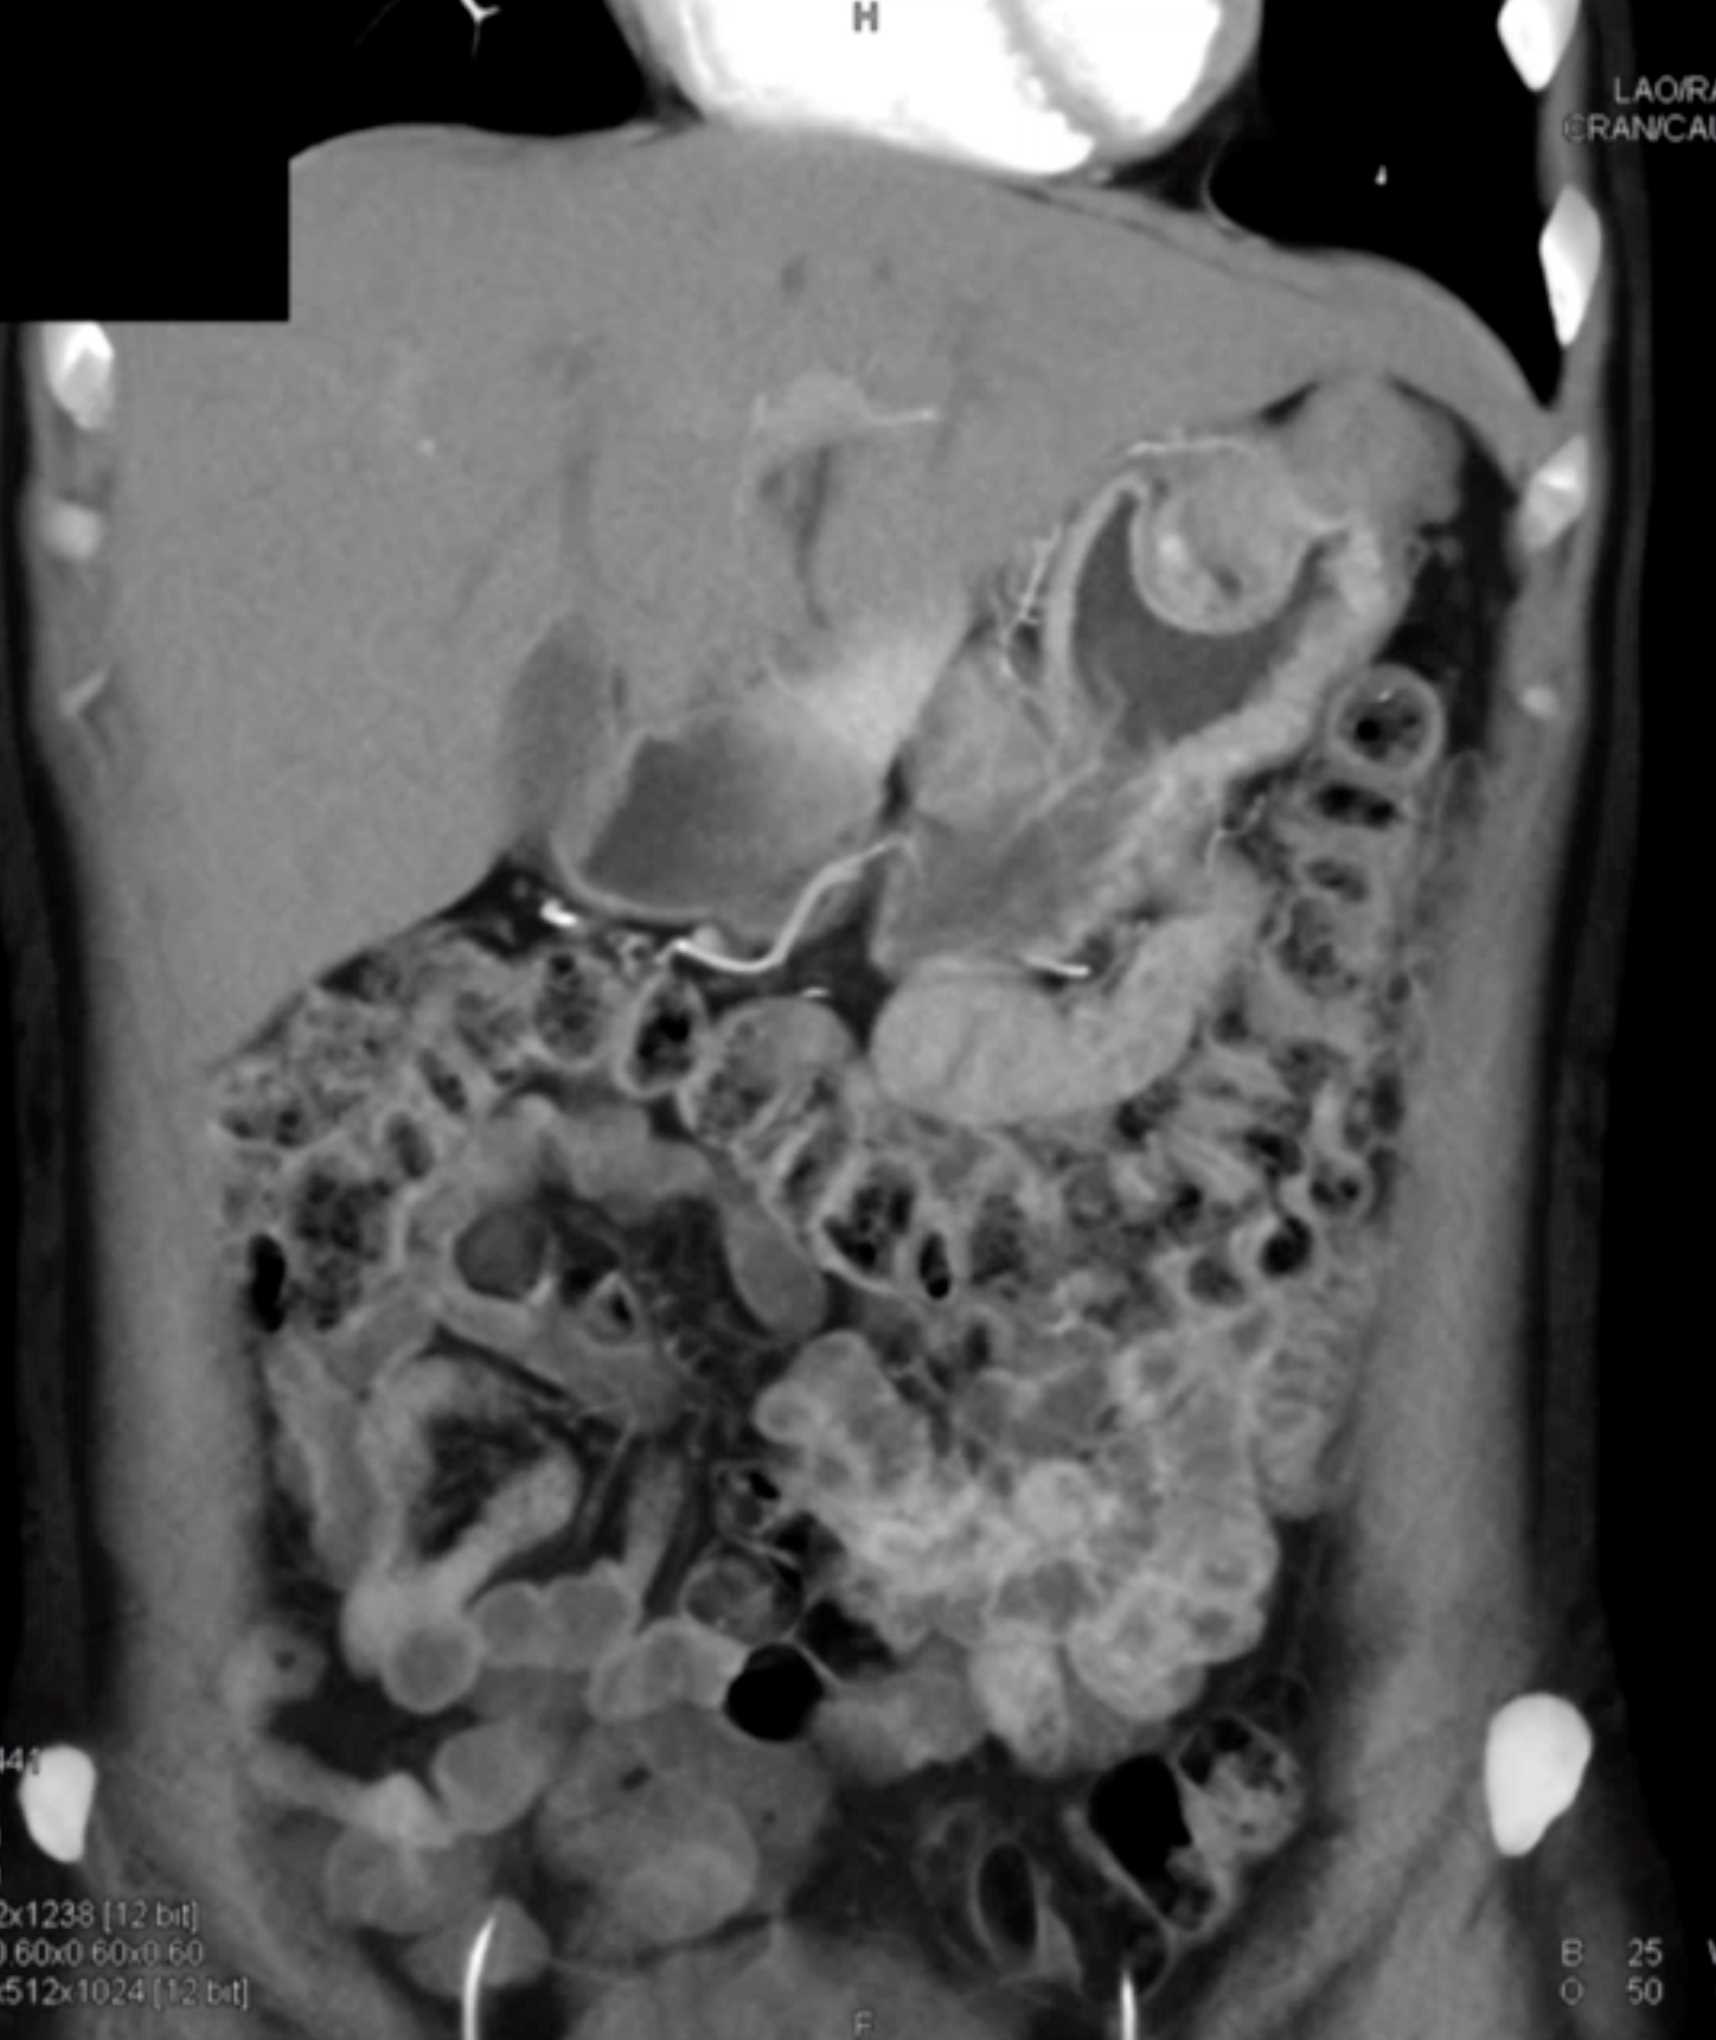

Multiple Gastric GIST Tumors with Spread to Nodes (Carney-Stratakis Syndrome)